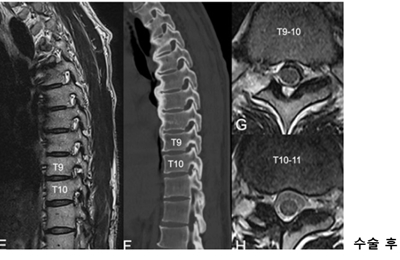

<»çÁø  ³»½Ã°æ ÈÄ¿ÜÃø Ãß°£°ø È®Àå¼ú »ç·Ê> °ú°Å °æÃß ÈıüºÇü¼ú°ú °³¹æÇü ÈäÃß µð½ºÅ©ÀýÁ¦¼úÀ» ¹ÞÀº ȯÀÚ, ÈäÃß 9~10¹ø°ú 10~11¹ø ºÎÀ§¿¡ Ãß°£°ø ÇùÂøÁõÀÌ ¹ß°ßµÅ ³»½Ã°æ ÈÄ¿ÜÃø Ãß°£°ø È®Àå¼ú·Î È£ÀüµÊ.